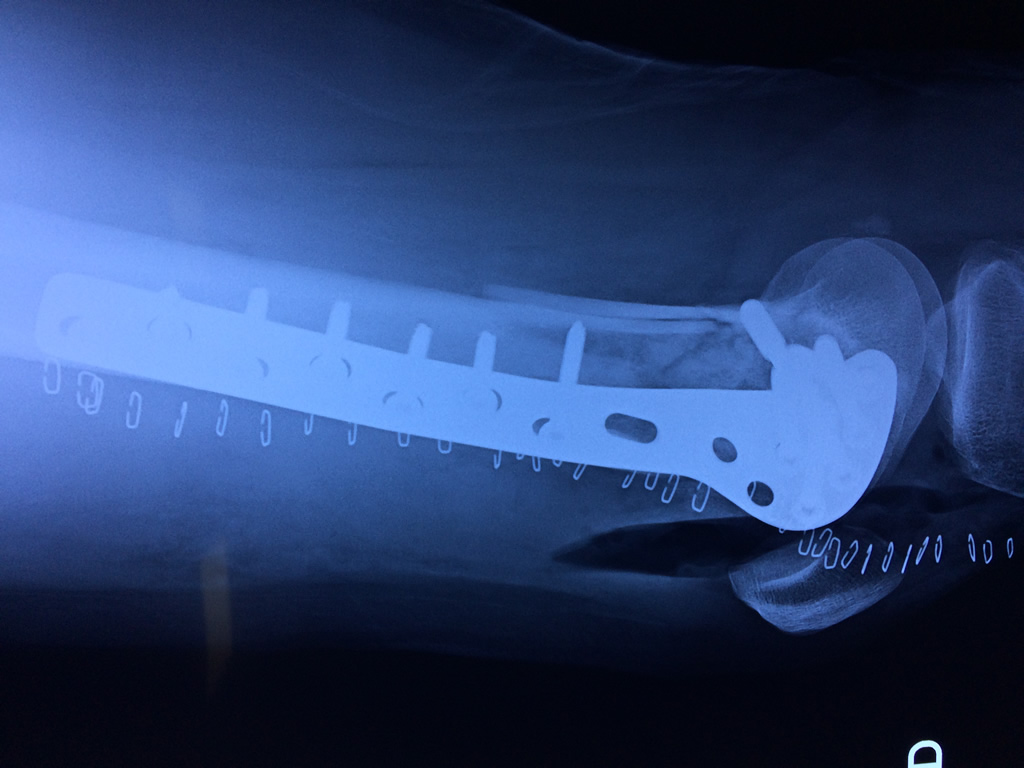

Cirugía de Fémur - Fémur

El fémur es el hueso del muslo, el segundo segmento del miembro inferior. Es el hueso más largo, fuerte y voluminoso del cuerpo humano.